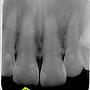

[問題] 請教斷層掃描能幫助了解補牙蛀牙情形嗎?

[ teeth_salon ]6 留言, 推噓總分: +2

6F推Tangut: 兩年間有去重補嗎09/03 16:36